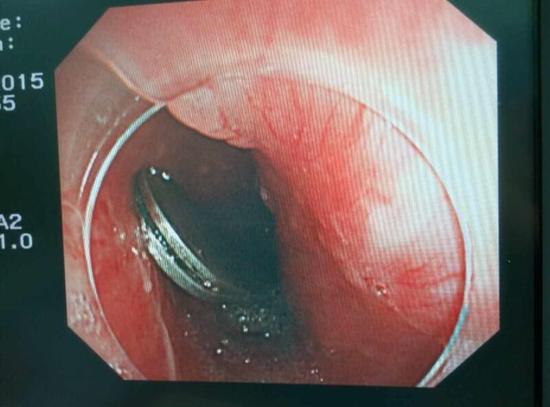

醫(yī)生從華先生胃里取出的鑷子和打火機(jī)

手術(shù)中,范醫(yī)生通過胃鏡準(zhǔn)確發(fā)現(xiàn)了胃里的鑷子。但讓他驚訝的是,在華先生胃底竟然還躺著三個被腐蝕了的打火機(jī),打火機(jī)的金屬部件都已經(jīng)不見了。

隨后,范醫(yī)生先用圈套器套取出了長10厘米的鑷子,再一個一個地取出了打火機(jī)。整個取出過程小心謹(jǐn)慎而又一氣呵成,只用了不到10分鐘。